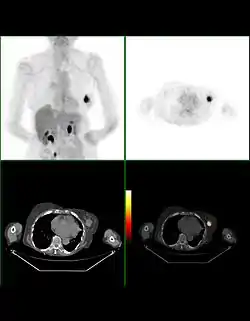

يعتبر التصوير المقطعي بالإصدار البوزيتروني (يرمز لها اختصاراً PET من Positron Emission Tomography) هي تقنية تصوير في الطب النووي تبين صور ثلاثية الأبعاد لبعض أعضاء الجسم وما قد يكون فيها من ورم سرطاني أو نقيلات سرطانية ، كما يمكن بواسطتها تفقد مختلف العمليات الوظيفية في الجسم، مثل العمليات الحيوية للجهاز الهضمي. ويعمل الجهاز المصوّر على أساس اكتشاف أزواج من أشعة غاما المنبثفة بشكل غير مباشر من نظير مشع يكون مصدرا للبوزيترونات (إلكترونات موجبة الشحنة) . يتم حقن المادة المشعة في جسم المريض بعد ربطه بجزيء حيوي فعال (مثل جزيء سكر) ، فتتركز المادة المشعة بالعضو المراد فحصه، مثل الدماغ أو الكلى أو الكبد . ثم يتم تسجيل القياسات لأشعة غاما الصادرة من العضو واستبناء صورة ثلاثية الأبعاد لها بواسطة الحاسوب، فيمكن رؤياها على شاشة متصلة بالحاسوب. في الآونة الأخيرة، أصبحت تستعمل طريقتين في نفس الوقت لزيادة التوضيح والاستبناء، وهي طريقتي التصوير الطبقي المحوسب بواسطة الأشعة السينية (أشعة إكس) وتكون مقترنة بالتصوير المقطعي بالإصدار البوزيتروني .

يُستخدم التصويرالصدري في تشخيص والكشف عن الأمراض القلبية وتبلغ درجة دقة الصور وحساسيتها أكثر من 90%.[3] المواد المشعة المستخدمة في هذا التصوير هي أكسجين-15 ونتروجين-13. هذا النوع من التصوير يعتبر باهظ الثمن عند مقارنته مع غيره من أساليب التصوير مثل التصوير بالرنين المغناطيسي أو التصوير بالمسح المقطعي، ولكن التصوير المقطعي القلبي بالإصدار البوزيتروني يتمتع بالعديد من الخاصيات التي تميزه عن بقية أنواع التصوير. التصوير الصدري يعتمد على ذات المبادئ والافتراضات التي تعتمد عليها بقية أنواع التصوير المقطعي بالإصدار البوزيتروني

ما الفرق بين MRI و PET و CT

يعطي جهاز PET معلومات عن الخلايا ووظائفها من خلال التمييز بين الخلايا والأنسجة النشيطة من ناحية الأيض في الجسم، وهذا شيء غير متوفر في الصور الناتجة عن جهاز التصوير المقطعي المحوسب CT وجهاز الرنين المغناطيسي MRI. التصوير المقطعي يستخدم الأشعة السينية، الرنين المغناطيسي يستخدم المجالات المغناطيسية، والتصوير المقطعي بالإصدار البوزيتروني يستخدم المواد المشعة مثل أوكسجين-15. بالإضافة إلى ذلك، لا ينتج جهاز PET صوراً تفصيلية لبنية الأعضاء كما هو الحال في CT أو MRI.[4]